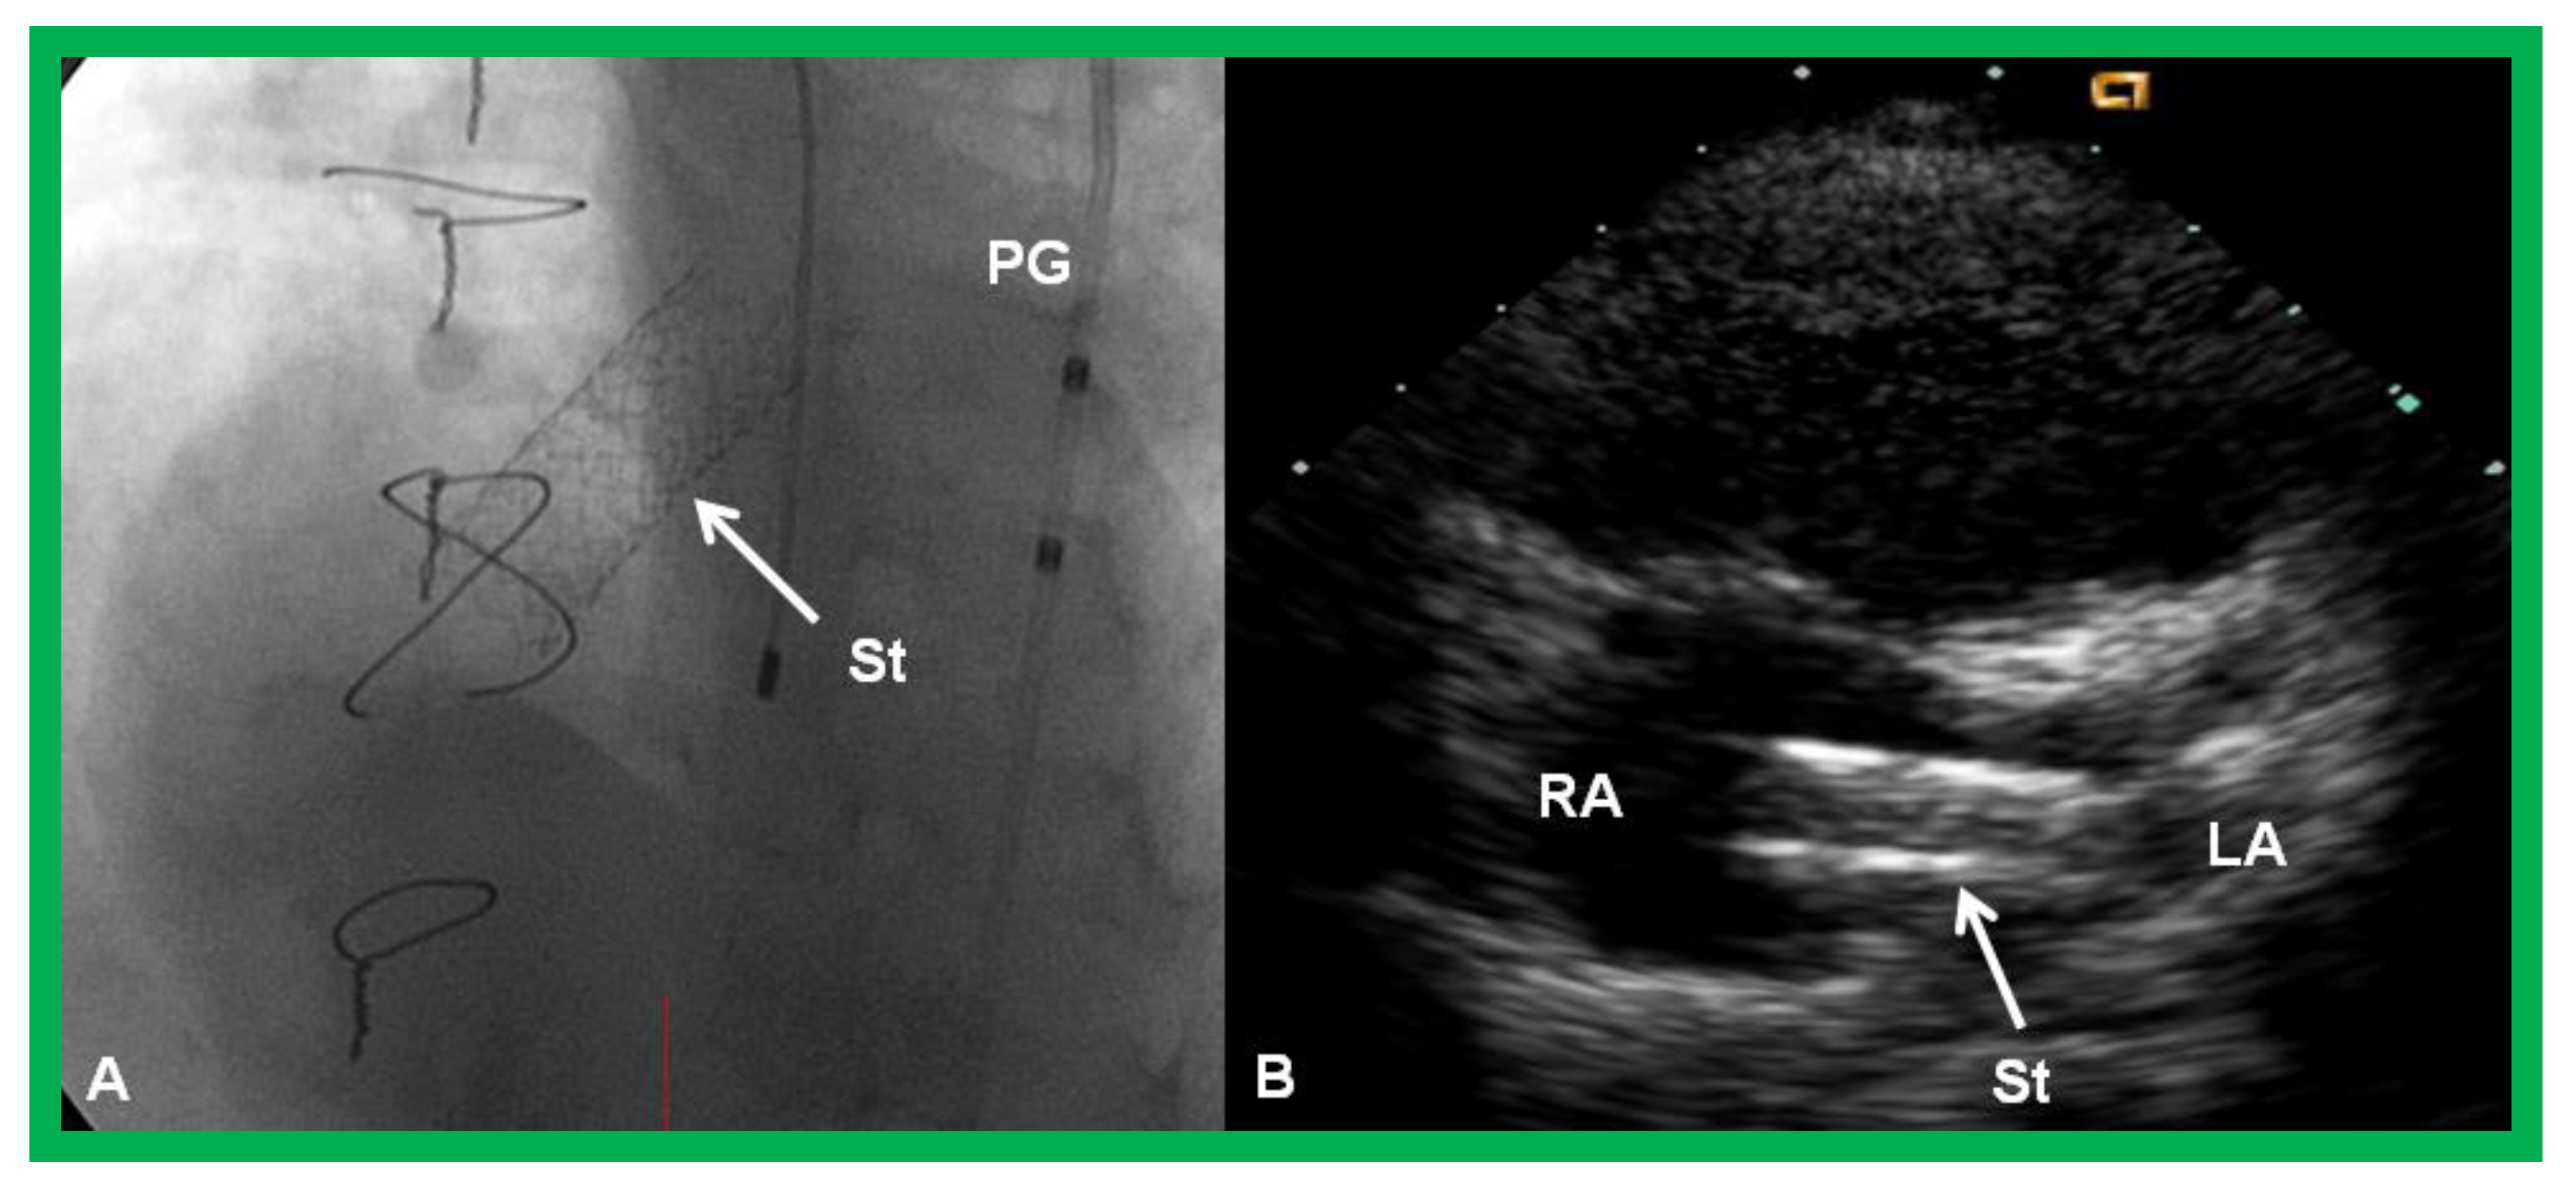

4.3.2. Stage IIIB

During the Stage IIIB, the fenestration is occluded (Figure 17) by transcatheter methods [33,81,83,84,85], usually 6–12 months following Stage IIIA Fontan. In the past, all previously available ASD occluding devices [81,83,84,85] were used for fenestration closure. However, at the present time, Amplatzer Septal Occluders are the most regularly used devices to accomplish fenestration closures. Any other residual shunts may also be addressed by device closure.

Figure 17.

(a). Cineangiogram in antero-posterior view, illustrating Stage IIIA of the Fontan operation, diverting the inferior vena caval (IVC) blood flow into the pulmonary arteries via a non-valve conduit (Cond). Fenestration (Fen) is shown by the arrow in (a). The Fen is occluded with an Amplatzer device (D), shown by the arrow in (b) (Stage IIIB). HV, hepatic veins; LPA, left pulmonary artery; RPA, right pulmonary artery. Reproduced from Reference [33].